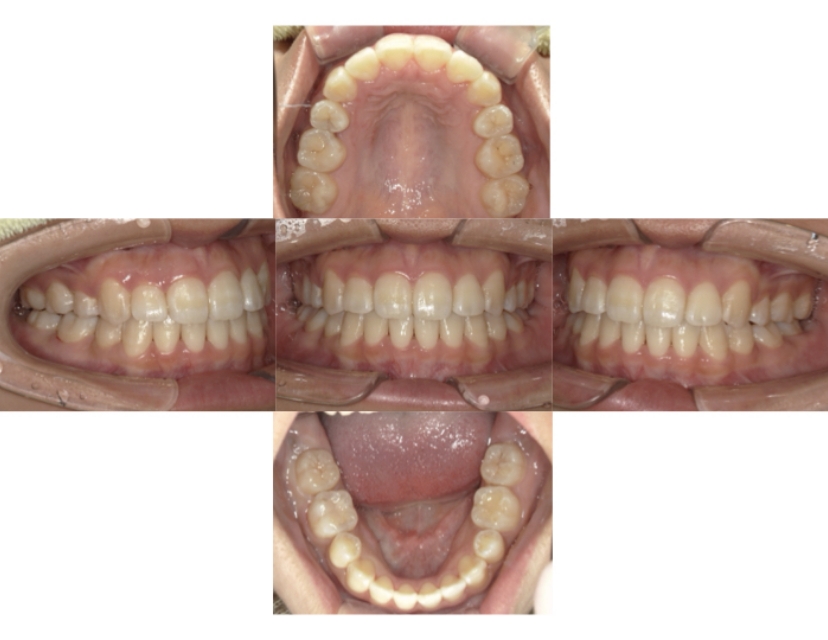

症例4

下顎前突、叢生

抜歯

ブラケット矯正

上下顎叢生、反対咬合(上下の前歯のガタガタ、若干受け口)のケースです。

装置はラビアル(上下表側)で、上下顎の小臼歯を4本抜歯を行っています。抜歯したスペースを使って、上下の叢生改善と前歯の受け口の改善を行っています。

主訴 前歯のガタガタを治したい。

年齢・性別 45歳 女性

お住まいの地域 神奈川県川崎市

治療方針 抜歯スペースを利用して上前歯の叢生(ガタガタ)の改善と受け口の改善

抜歯部位 上顎左右第一小臼歯、下顎左右第二小臼歯

使用装置 ラビアル(上下表側)、顎間ゴム

治療期間 2年6か月

治療回数 20回

リテーナー クリアリテーナー

BEFORE

AFTER